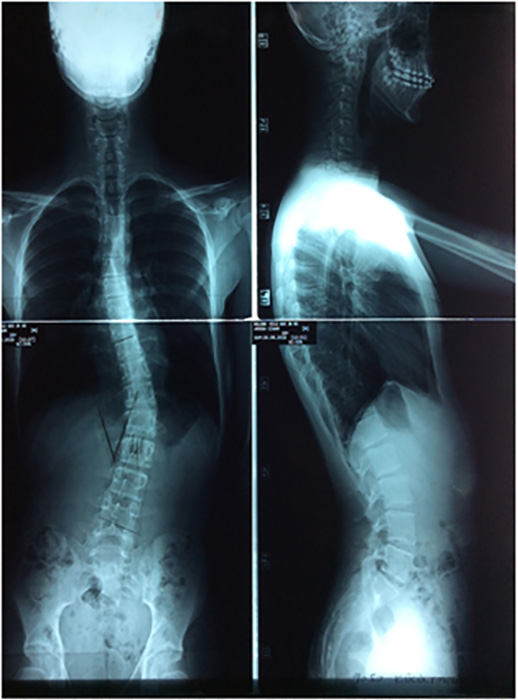

KORSE ÖNCESİ - SONRASI 2

korseler-2